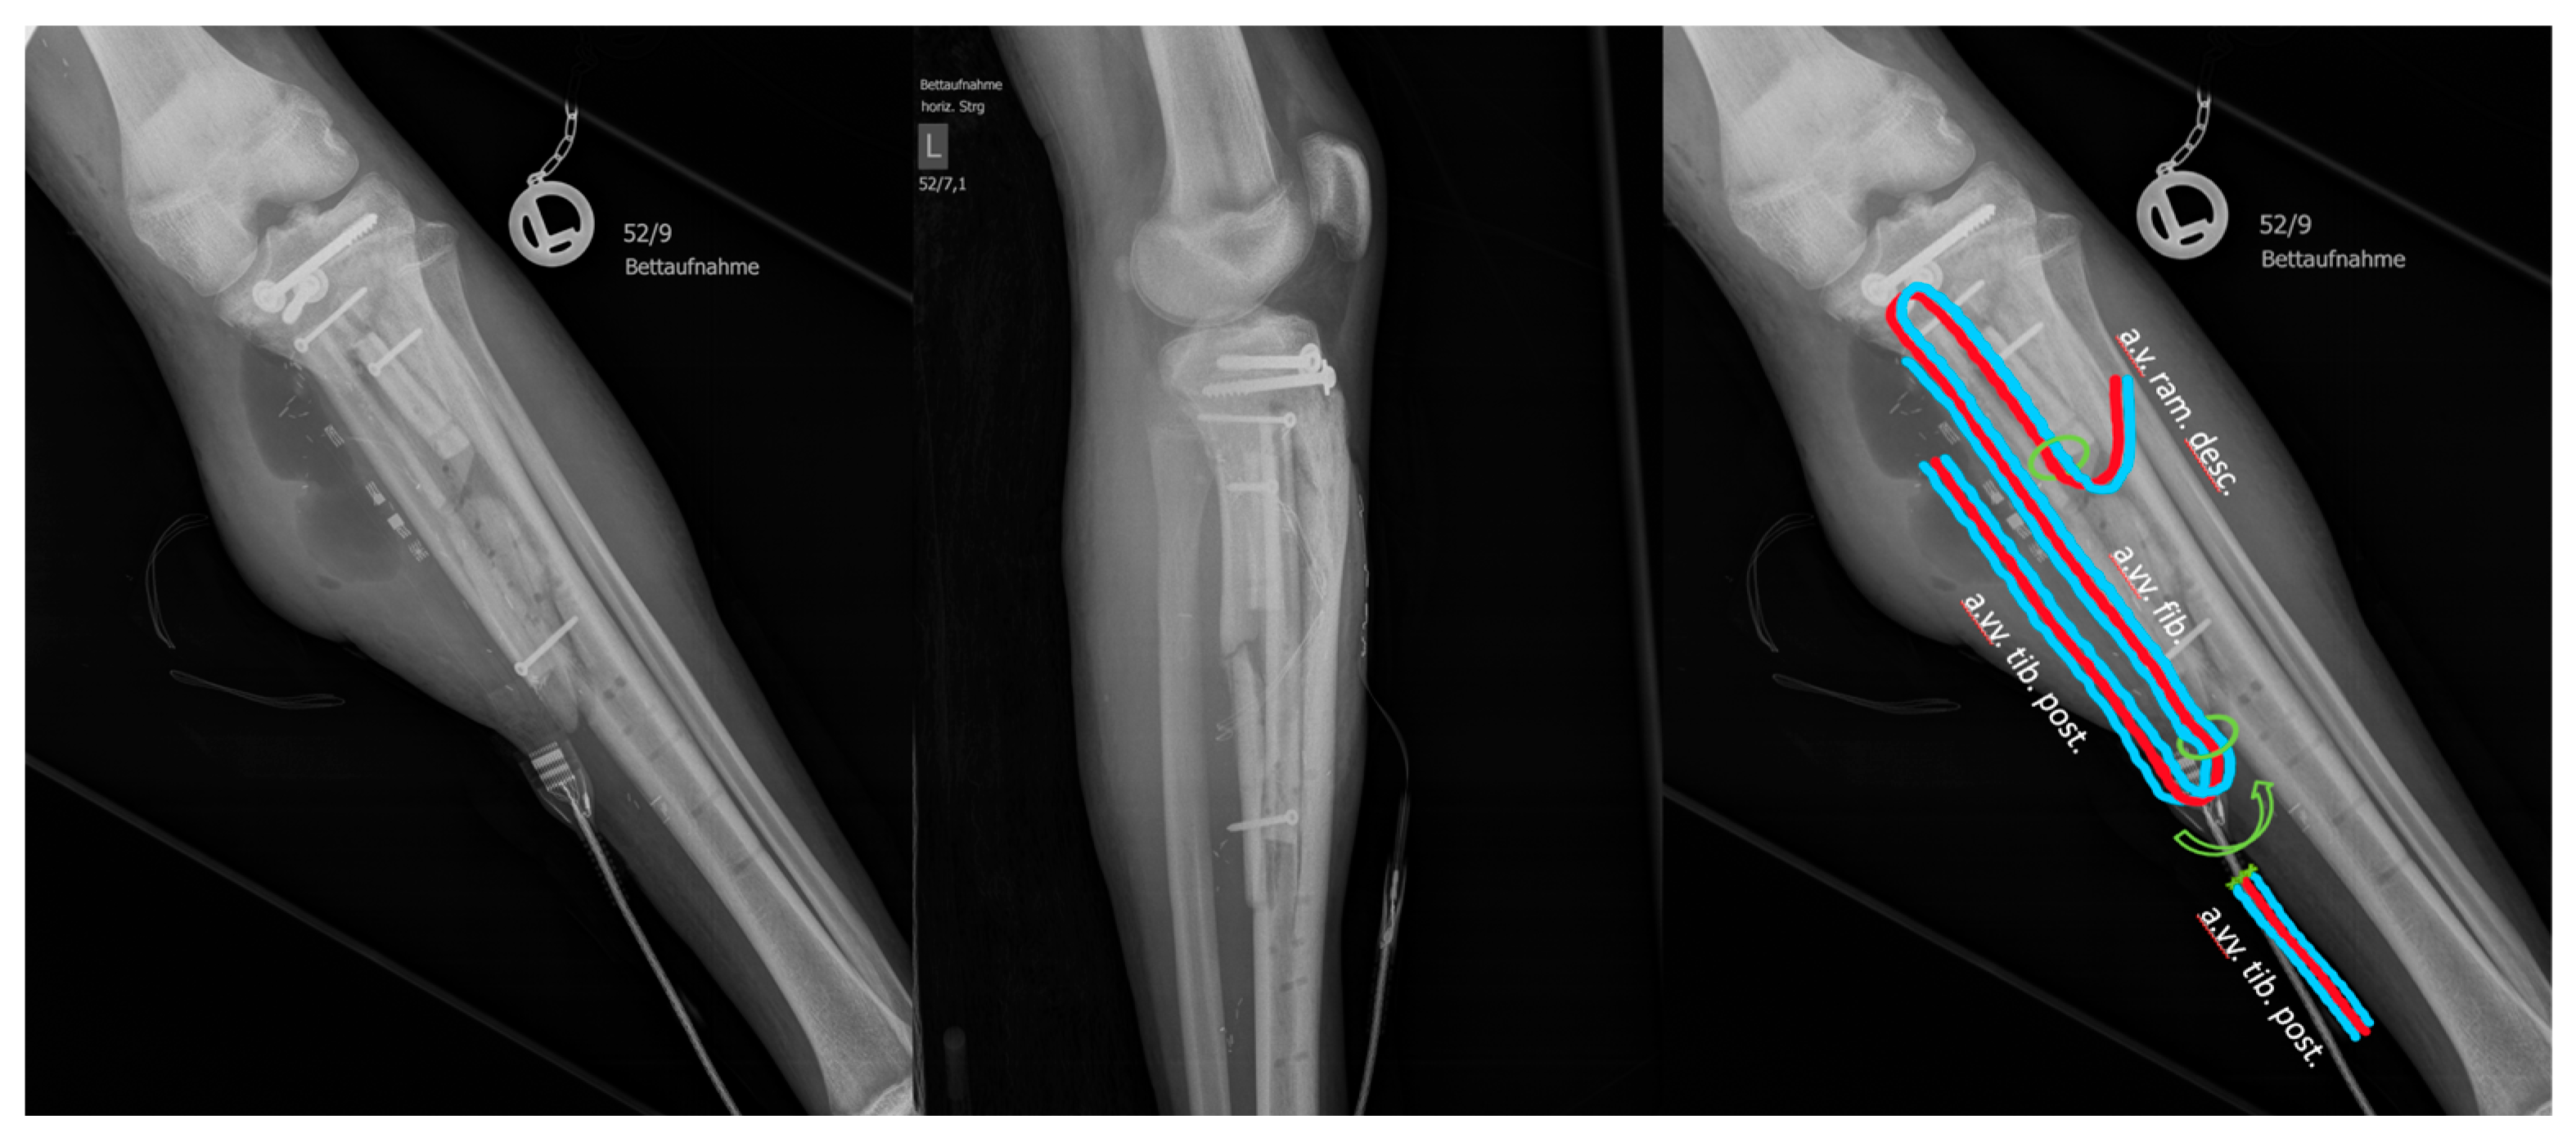

2. Case Description